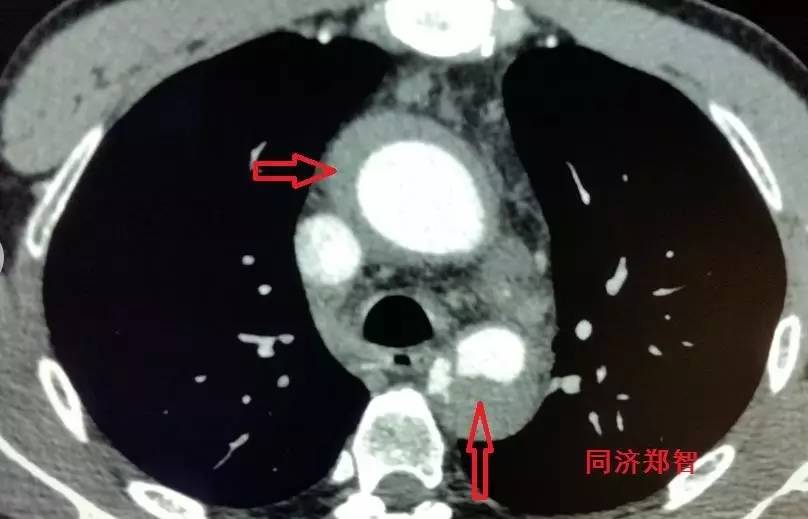

CTA显示降主动脉穿透性溃疡合并Stanford A型主动脉壁间血肿(图14)。

图14